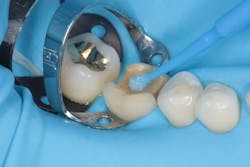

In addition to optimal bonding, the rubber dam may retract the tissues when placed properly, improving our visualization of finish lines, margins, and adhesive materials. One of dentistry’s rubber dam advocates, Dr. Hunter Brinker (the inventor of the B1-B6 clamps), often said “to see is to know” when referring to the benefits of the rubber dam to improve attention to detail through better visual access. It is interesting to note that when the rubber dam is properly placed, it will not only retract the tongue, lips, and cheeks, but it will also atraumatically retract the gingiva, typically 2–3 mm, and expose areas that could not be visualized by any other nonsurgical means (figures 3–5).